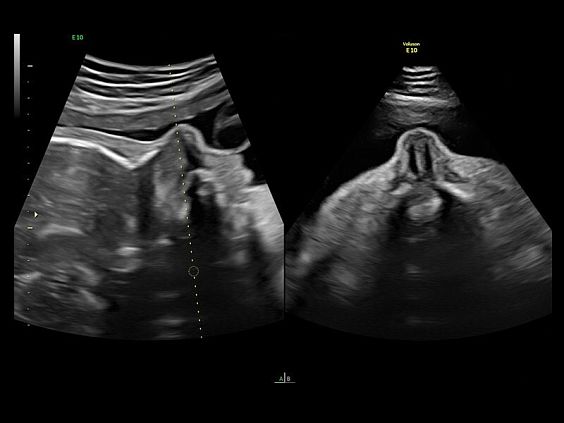

• Томографический ультразвук (TUI)

• Объемное контрастирование прямой плоскости - Basic VCI (VCI-A + VCI static)

• Режим бипланового сканирования Bi-Plane в В-режиме и ЦДК.

• Advanced VCI (Volume Contrast Imaging) - расширенный программный пакет объемного контрастного изображения (VCI) для механических и электронных объемных датчиков:

• Проведение любой произвольной плоскости в 3D/4D (OmniView)

• Объемное контрастирование любой произвольной плоскости (OmniView+VCI)

• Регулировка толщины и формы коронарного среза в 3D/4D (получение коронарной плоскости в 3D/4D, например, для оценки мозолистого тела - автоматическая функция "Corpus Callosum"